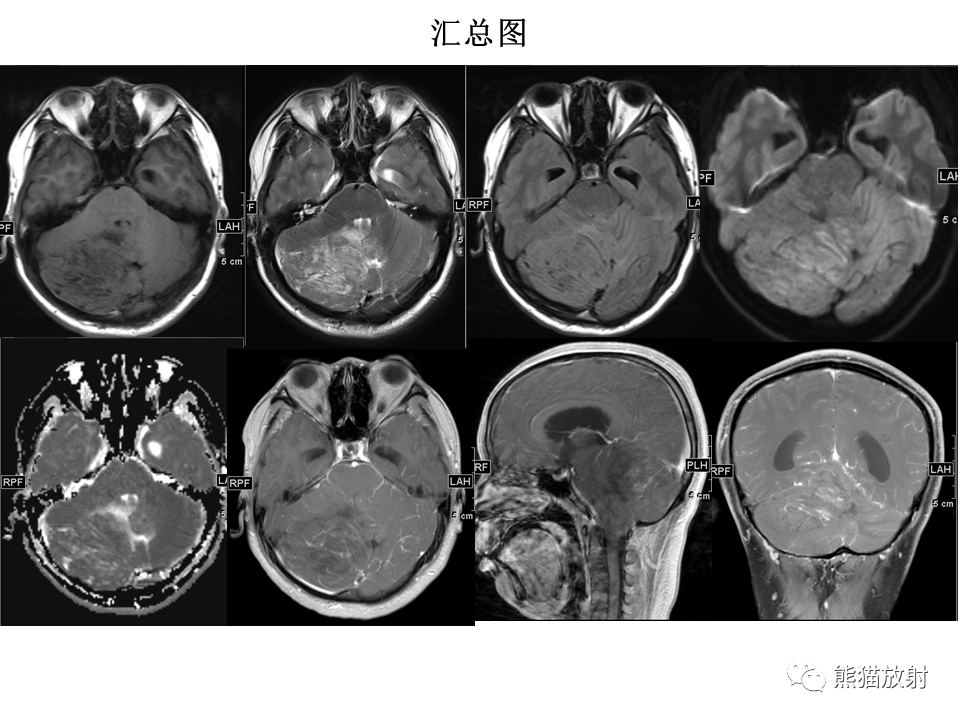

【PPT】小脑发育不良性神经节细胞瘤 VS 成人型髓母细胞瘤-4